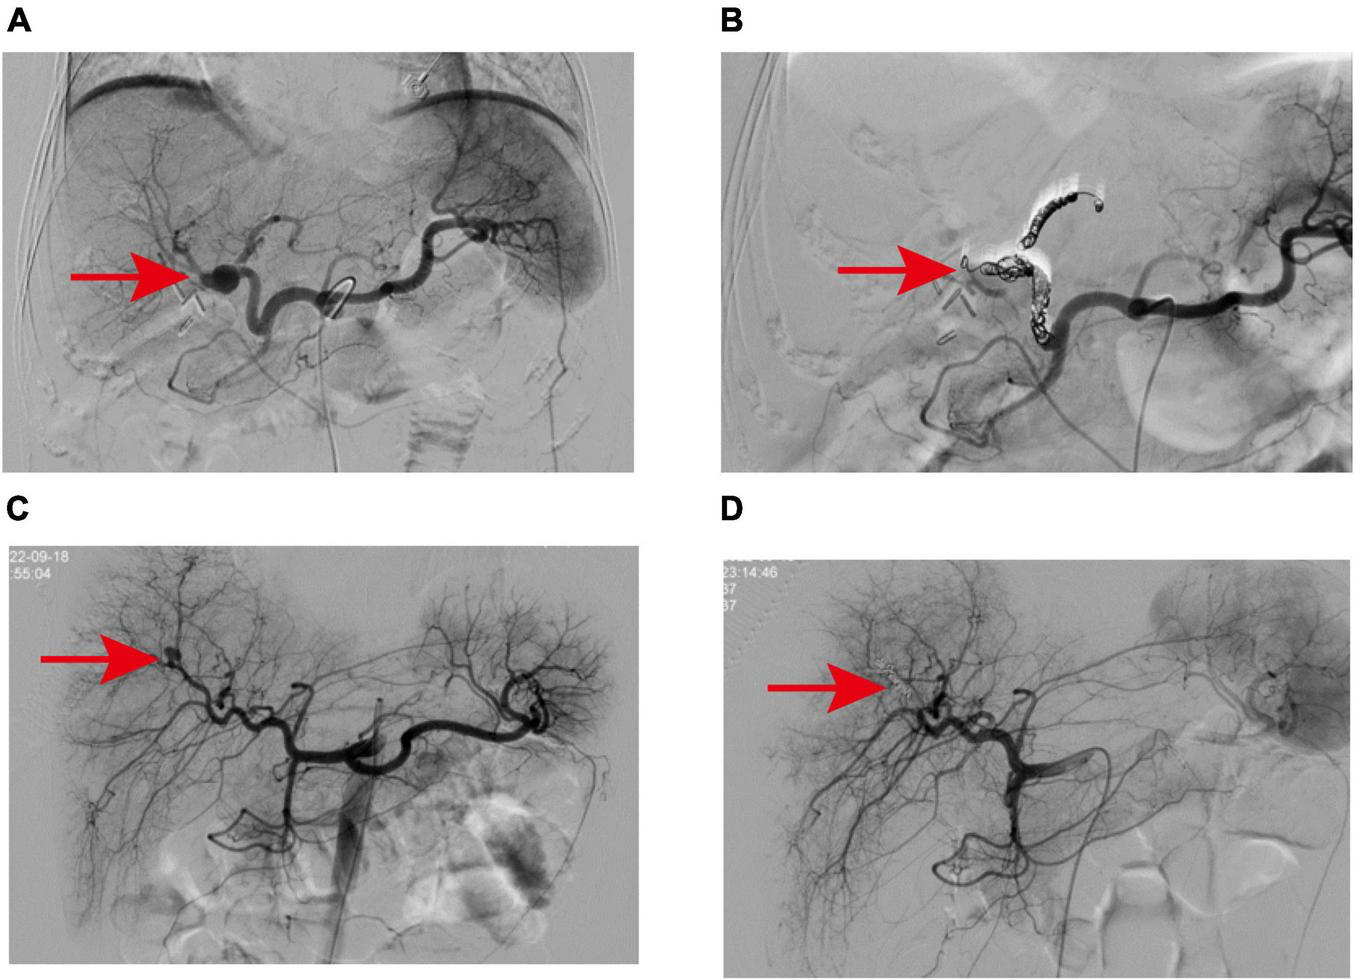

A 79-year-old male patient was admitted to the hospital as an emergency case due to bleeding from the T-tube with somnolence 2 weeks after undergoing laparoscopic surgery for cholelithiasis treatment. The patient has a history of type 2 diabetes and underwent lumbar surgery in 2018. A little over half a month ago, at our institution, the patient underwent laparoscopic common bile duct exploration with T-tube drainage and cholecystectomy. Routine blood tests showed Hb 62 g/L, and emergency computed tomography (CT) of the abdomen revealed an accumulation of blood around the T-tube, liver, and spleen, and accumulated fluid in the abdominal cavity. Subsequently, fasting, fluid replacement, blood transfusion, and hemostatic drugs (ethamsylate, tranexamic acid, and snake venom thrombin) were performed, however, the patient continued bleeding and underwent digital subtraction angiography (DSA), more precisely selective hepatic arteriography. This led to the identification of an isolated pseudoaneurysm, approximately 1.5 cm in diameter, originating distally from the main trunk of the right hepatic artery (approximately 1.0 cm from the bifurcation) (Figure 1A). In this case, to preserve the blood flow of the right hepatic artery and to avert the risk of fatal hepatic necrosis and hemorrhage consequent to the rupture of the pseudoaneurysm, the endovascular covered stent was prioritized for the treatment of HAP. Therefore, the endovascular covered stent placement was performed. A heparin-coated peritoneal stent (GORE, VBHR 050202W) was successfully placed distal to the right hepatic artery trunk and expanded using a 5 mm × 60 mm balloon (COOK, USA). Angiography reexamination demonstrated that contrast medium overflow could be seen at the distal end of right hepatic artery trunk, and arterial stent implantation failed. Subsequently, the patient underwent an emergent transcatheter arterial embolization (TAE) procedure. A microcatheter was advanced to the distal right hepatic artery, and Microcoils (COOK, USA) were deployed to embolize the pseudoaneurysm distally. Angiography confirmed successful embolization with no contrast flow into the pseudoaneurysm and normal right hepatic artery perfusion (Figure 1B). To prevent thrombosis after endovascular covered stent placement, the patient was administered anticoagulant therapy (specifically, Rivaroxaban 10 mg once daily) for a continuous period of 2 months, and antiplatelet therapy (specifically, Aspirin enteric-coated tablets 100 mg once daily) for a duration of 1 year.

(A) Angiography revealed a pseudoaneurysm at the distal end of the right hepatic artery trunk. (B) The pseudoaneurysm was successfully embolized with Microcoils. (C,D) CT scan indicated that the pediatric patient had liver contusion with surrounding hematoma formation.

A 57-year-old female patient was admitted to the hospital 4 weeks after undergoing laparoscopic surgery to treat cholelithiasis. The main complaint was T-tube bleeding 7 days after cholelithiasis surgery. The patient’s medical history indicates a prior lumbar surgery conducted in 2015, and 1 month prior, at our hospital, the patient underwent a laparoscopic common bile duct exploration with T-tube drainage and cholecystectomy. On admission, the patient had severe anemia (Hb 52 g/L), listlessness, and pale skin. Consequently, active blood transfusion, administration of hemostatic drugs (ethamsylate, tranexamic acid, and snake venom thrombin), and intravenous infusion were performed which slightly improve the patient’s symptoms. Initially, we suspected upper gastrointestinal bleeding and thus performed an upper gastrointestinal endoscopy which suggested chronic non-atrophic gastritis. After aggressive conservative treatment, the patient’s condition stabilized. On day 7 after admission, the patient experienced a sudden onset of hematemesis, darkred, with a volume of approximately 200 ml, accompanied by T-tube drainage of bloody fluid, abdominal pain, and fever (38.9°C). Emergency laboratory tests revealed a white blood cell count of 25.83 × 109/L, Hb 64 g/L, and the patient received blood transfusions, gastrointestinal decompression, anti-infection, intravenous infusion, among other interventions. A blood routine examination the next day showed a cell count of 9.35 × 109/L and Hb 68 g/L, however, the patient showed bright red bloody fluid outflow from the T-tube. Based on these findings, we suspected that the patient still had active hemorrhage. Subsequently, we performed an emergency elective hepatic arteriography on the patient. A 2.0 cm solitary pseudoaneurysm with aneurysmal dilation was identified at the confluence of the left and right hepatic arteries. Extensive collateral circulation surrounded the left hepatic artery trunk and the two branches of the right hepatic artery (Figure 2A). Further analysis showed that the endovascular covered stent placement was not suitable for this patient because the HAP was present at the intersection of the left and right hepatic arteries, there were multiple tortuous collateral vessels, and its size was not appropriate for the currently marketed covered stent. Therefore, we performed TAE on patients. Multiple tortuous collateral vessels were successfully embolized using Microcoils (COOK, USA) (Figure 2B). Following TAE, with the support of our nursing team, we provided the patient with comprehensive postoperative care akin to that administered in case 1. Ultimately, all biochemical indicators of the patient returned to normal, and the patient was discharged after the T-tube was successfully removed. During the outpatient follow-up visit 1 month postoperatively, the patient was disease-free and in good condition.

(A) The pseudoaneurysm was located at the bifurcation of the left and right hepatic arteries and showed multiple collateral circulation, which was related to the two branches of the left hepatic artery trunk and the right hepatic artery. (B) Microcoils were successfully used to embolize the vessels from the left hepatic artery to the neck of the aneurysm and from the branches of the right hepatic artery to the distal branches of the proper hepatic artery. (C) Angiography revealed a pseudoaneurysm in a branch of the right hepatic artery. (D) After embolization of pseudoaneurysms with Microcoils and embolic particles, the contrast extravasation disappeared.

A 6-year-old girl was admitted to the emergency department due to abdominal pain after trauma. The patient’s medical history is unremarkable. The patient had no bloody stool or hematuria at admission, and a CT examination performed immediately revealed a possible formation of liver contusion and perihepatic hematoma (Figures 1C, D). After symptomatic support treatment, the child’s condition gradually improved. After 6 days of admission, she developed suddenly hematemesis, melena, and hemorrhagic shock. Thus, she was transferred to the pediatric intensive care unit for further treatment. Blood transfusion was conducted and hemostatic drugs were prescribed. The gastrointestinal endoscopy was performed immediately and suggested the possibility of blood pooling in the intestinal lumen of the small intestine. To determine the cause of bleeding, we subsequently performed selective hepatic arteriography. The right hepatic artery branch was found to be damaged and a significant pseudoaneurysm was formed (Figure 2C), measuring about 1.2 cm in diameter, and contrast medium overflow was detected. Subsequently, we performed emergency TAE, successfully embolizing the feeding branch of the HAP with Microcoils (COOK, USA) and embosphere microspheres (Figure 2D). Following TAE, we provided the child with comprehensive postoperative care tailored to her condition, akin to the care administered in case 1. One week post-procedure, the patient’s blood routine and liver function indices returned to normal, facilitating a smooth discharge. Upon outpatient follow-up 1 month later, the child exhibited no adverse symptoms and maintained normal blood routine and liver function.